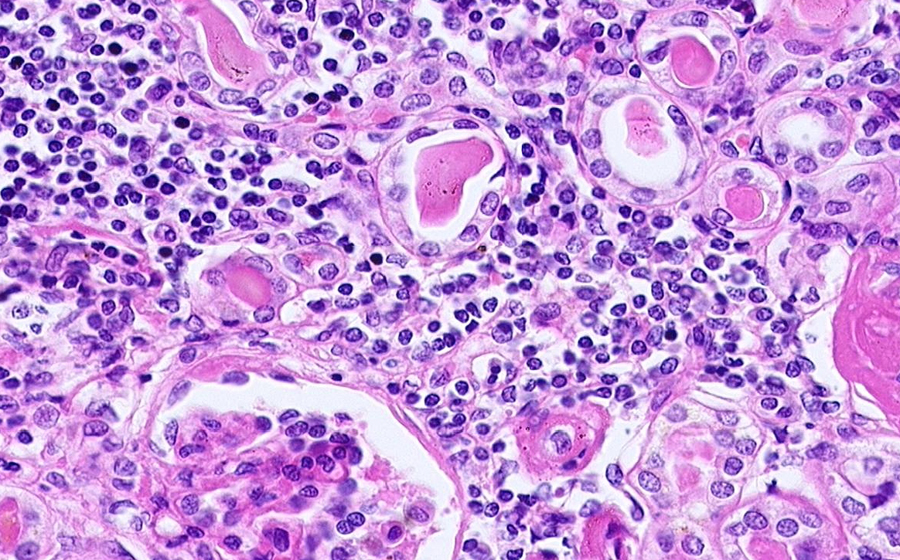

Slide 3: Glomerulonephritis - chronic

Histologic section of kidney from a patient with chronic glomerulonephritis. (click here to review normal tissue)

Image 4 - 100X

Slide 3 - Image 4